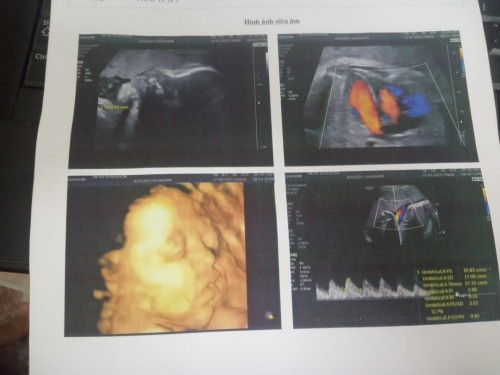

Các mom ơi, e đi SA mà 3 hìh đen khác vs hìh màu ở phần trên về số tuần thai, ko biết có nhầm ảnh ko

siêu âm có chênh lệch nhé. Nên lấy tuần 12 làm chuẩn thôi. S.a bác sĩ ko nói j thì bt thôi mom

sa màu khác với sa đen trắng. sa đen trắng thường là chuẩn hơn